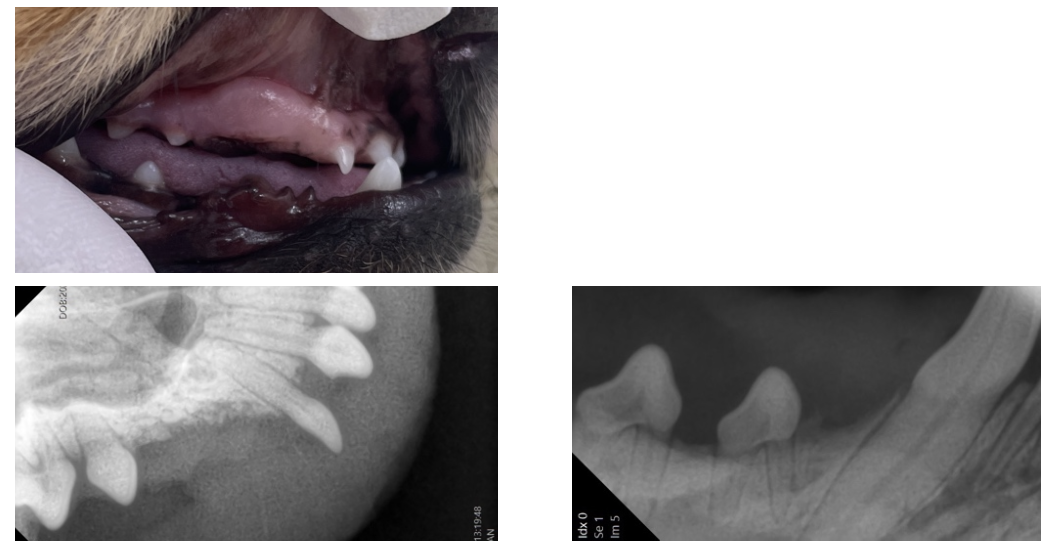

歯肉を切開すると、写真のように歯が歯肉の下に埋まっていたことがわかります。